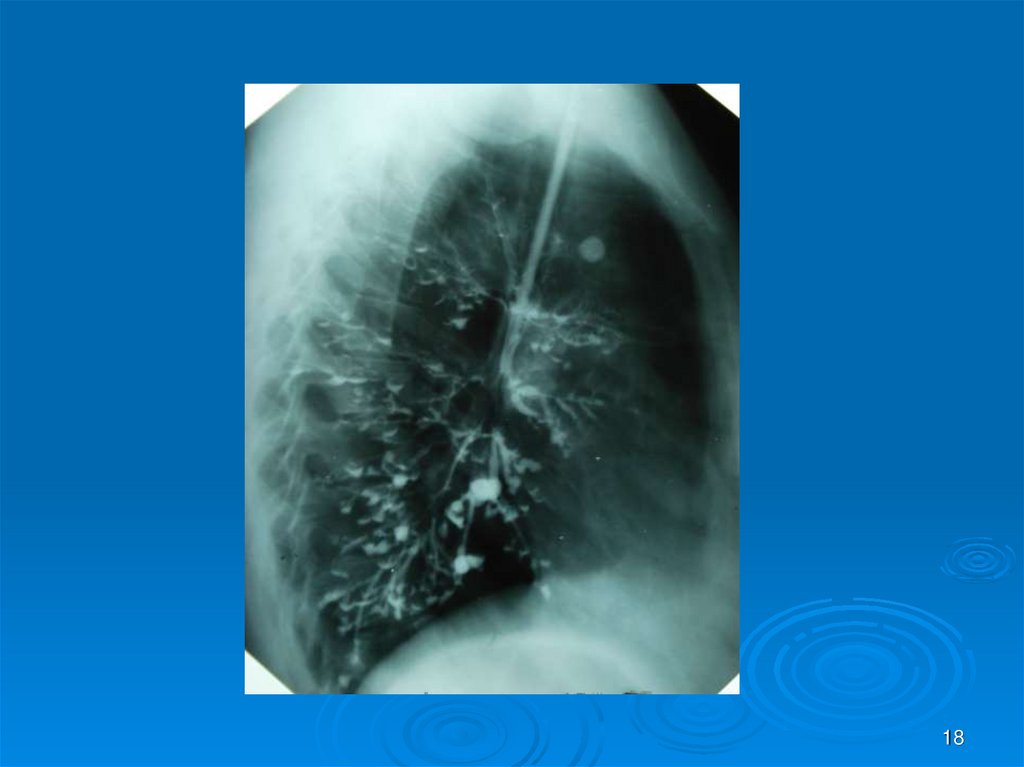

18.

18